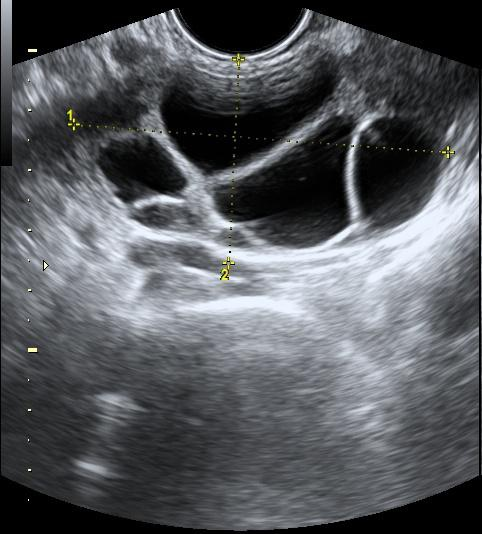

US imaging presents a substantial domain gap compared to other medical imaging modalities; building an US-specific foundation model therefore requires a specialized large-scale dataset. To build such a dataset, we crawl a multitude of platforms for human medical US with instance annotations and open-access availability: Papers with Code, Google Dataset Search, GitHub, Google Scholar, Kaggle, ResearchGate, Mendeley dataset, Zenodo and Data in Brief. Through this process, we arrive at US-43d (see Fig.1.a), a collection of 43 datasets covering 20 different clinical applications, containing 282,321 annotated segmentation masks from both 2D and 3D scans. US-43d captures organs and lesion of various shapes, sizes, and textures across clinical applications such as cardiac, fetal head, thyroid, and breast lesions, as illustrated in Fig.2, providing a comprehensive view of the medical ultrasound landscape. Table 1 provides detailed information on the US-43d dataset, including dataset names, access links, and the number of images and segmentation masks available in each.

For testing, we select three diverse datasets from US-43d: BUS-BRA [BUSBRA] (breast lesions, 1875 images), MMOTU2D [mmotu] (ovarian lesions, 1469 images), and GIST514-DB [GIST514] (gastrointestinal stromal tumors, 514 images). GIST514-DB is included as an outlier in our selection, as it is the only dataset in US-43d with radial acquisition. We evaluate on the official test split of each dataset. Together they include linear and radial probes, endoscopic and non-endoscopic US, and span multiple clinical applications, anatomical regions, lesion types, and imaging techniques, enabling exhaustive evaluation of UltraSam’s generalizability. We reserve 5% of each training dataset for validation and use the remaining 95% for training. We preprocess images by removing label-background overlaps (common in 3D US), cropping backgrounds occupying more than 50% of image pixels, and using sagittal views for 3D images.